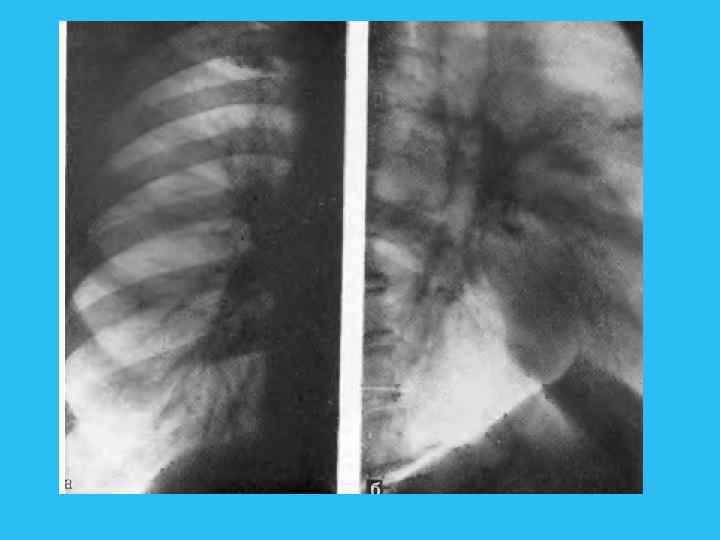

Рентгенологически проявлением этой стадии является сегментарное вздутие, которое развивается по мере дальнейшего роста опухоли и суже ния просвета бронха. Поскольку в фазе выдоха просвет бронха суживается, происходит накопление остаточного воздуха в сегменте и его прогрессирующее вздутие. Эта фаза нарушения бронхиальной проходимости лучше прослеживается в фазе максимального выдоха (рис. 228). Рис. 228. Обеднение сосудистого ри сунка в правом легком. Прямая рентгенограмма. а — фаза вдоха; б — фаза выдоха: вздутие правого легкого» смещение средостения влево.

Применение функциональных проб позволяет заметить смещение средостения в фазе выдоха в противоположную сторону. Анализ легочного рисунка в этой фазе показывает, что соответственно пораженным участкам заметно обеднение сосудистого рисунка из за веерообразного раздвигания сосудистых ветвей и уменьшения кровенаполнения, вследствие повышенного внутриальвеолярного давления. По мере роста опухоли наступает четвертая фаза. Последняя связана с полным перекрытием просвета бронха, чему способствует скопление в нем слизи, мокроты и крови. Все эти факторы рано или поздно приводят к III стадии нарушения бронхиальной проходимости, к возникновению ателектаза (рис. 229). Именно сложный характер пробки, обтурирующей бронх, является одной из причин так называемых перемежающихся ателектазов. Стадия ателектаза обычно диагностируется при поражении зональных и долевых бронхов и реже при сегментарных. Сегментарные поражения часто расцениваются как проявления пневмонии, и лишь тогда, когда развивается ателектаз зоны или доли, устанавливается диагноз рака легкого. Описанные фазы нарушения бронхиальной проходимости от гиповентиляции через клапанное вздутие к ателектазу также последовательно наступают и при развитии опухоли в зональных долевых и главных бронхах.

Рис 229. Ателектаз переднего сегмента верхней доли слева. а — прямая рентгенограмма; 6 — боковая томограмма. Сужение устья переднесегментарного бронха.